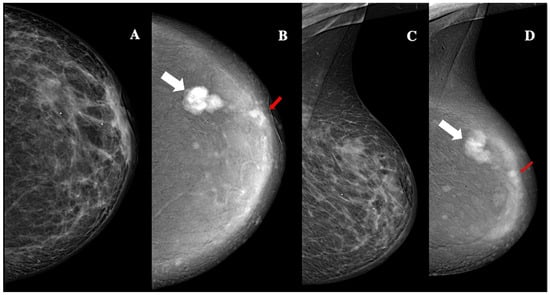

Contrast-enhanced mammography of a 63-year-old patient with BI-RADS 5 lesion. Panel (A,C) show a low-energy MLO view, highlighting dense breast parenchyma. Panel (B,D) display the corresponding recombined image, revealing a 24 mm oval lesion with non-circumscribed margins, heterogeneous enhancement, high conspicuity (white arrows), and an additional 8 mm oval lesion with circumscribed margins, homogeneous enhancement, and low conspicuity (red arrows). These findings are consistent with unilateral, multifocal, grade 3, triple-negative ductal cancer, with lymphovascular invasion.